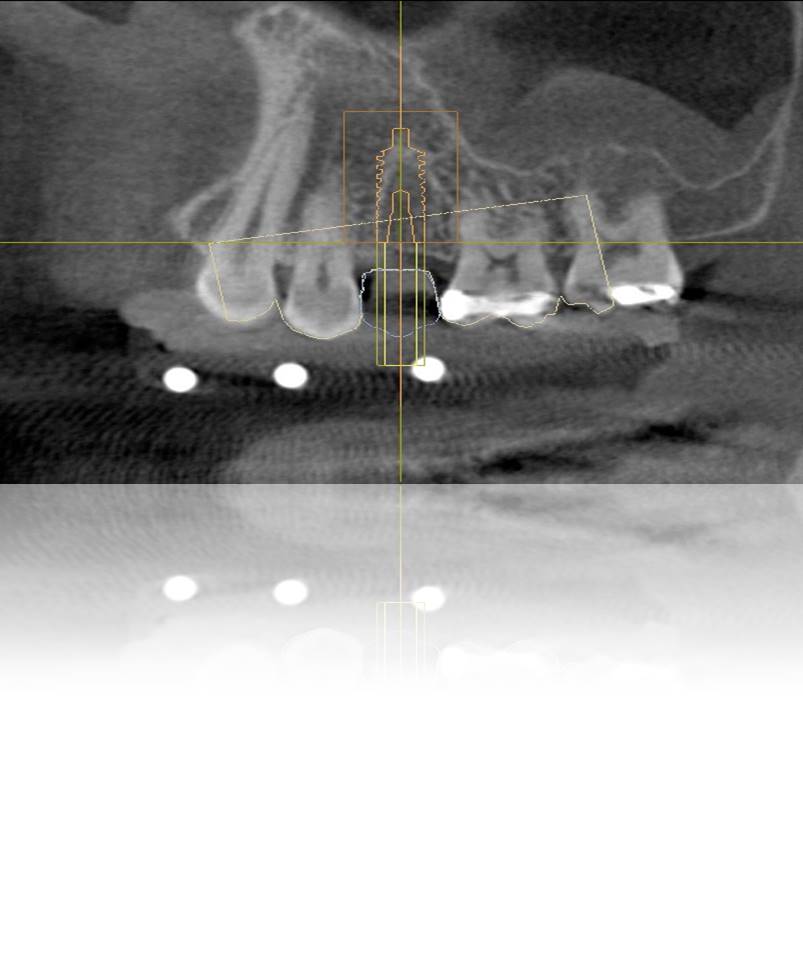

Figure 6. View of the digitized treatment plan, illustrating implant angulation, restoration placement, and access hole alignment if original plan is altered.

Figure 6

Figure 7. View of the corrected treatment plan, illustrating proper implant angulation, ideal restoration placement, and correct access hole alignment/location.

Figure 7

Therefore, pre-planning multiple aspects of the implant treatment, as well as the different components of the restoration, can help to ensure precise placement and angulation, as well as proper fit and connection of the implant abutment and restoration.19,20 Implant position, angulation, and restoration margin placement can be ideally planned based on preoperative analysis (eg, CBCT, planning software), and the anticipated outcomes achieved using surgical templates, guided surgery, and virtual/traditional restoration models (Figure 1 through Figure 7).21